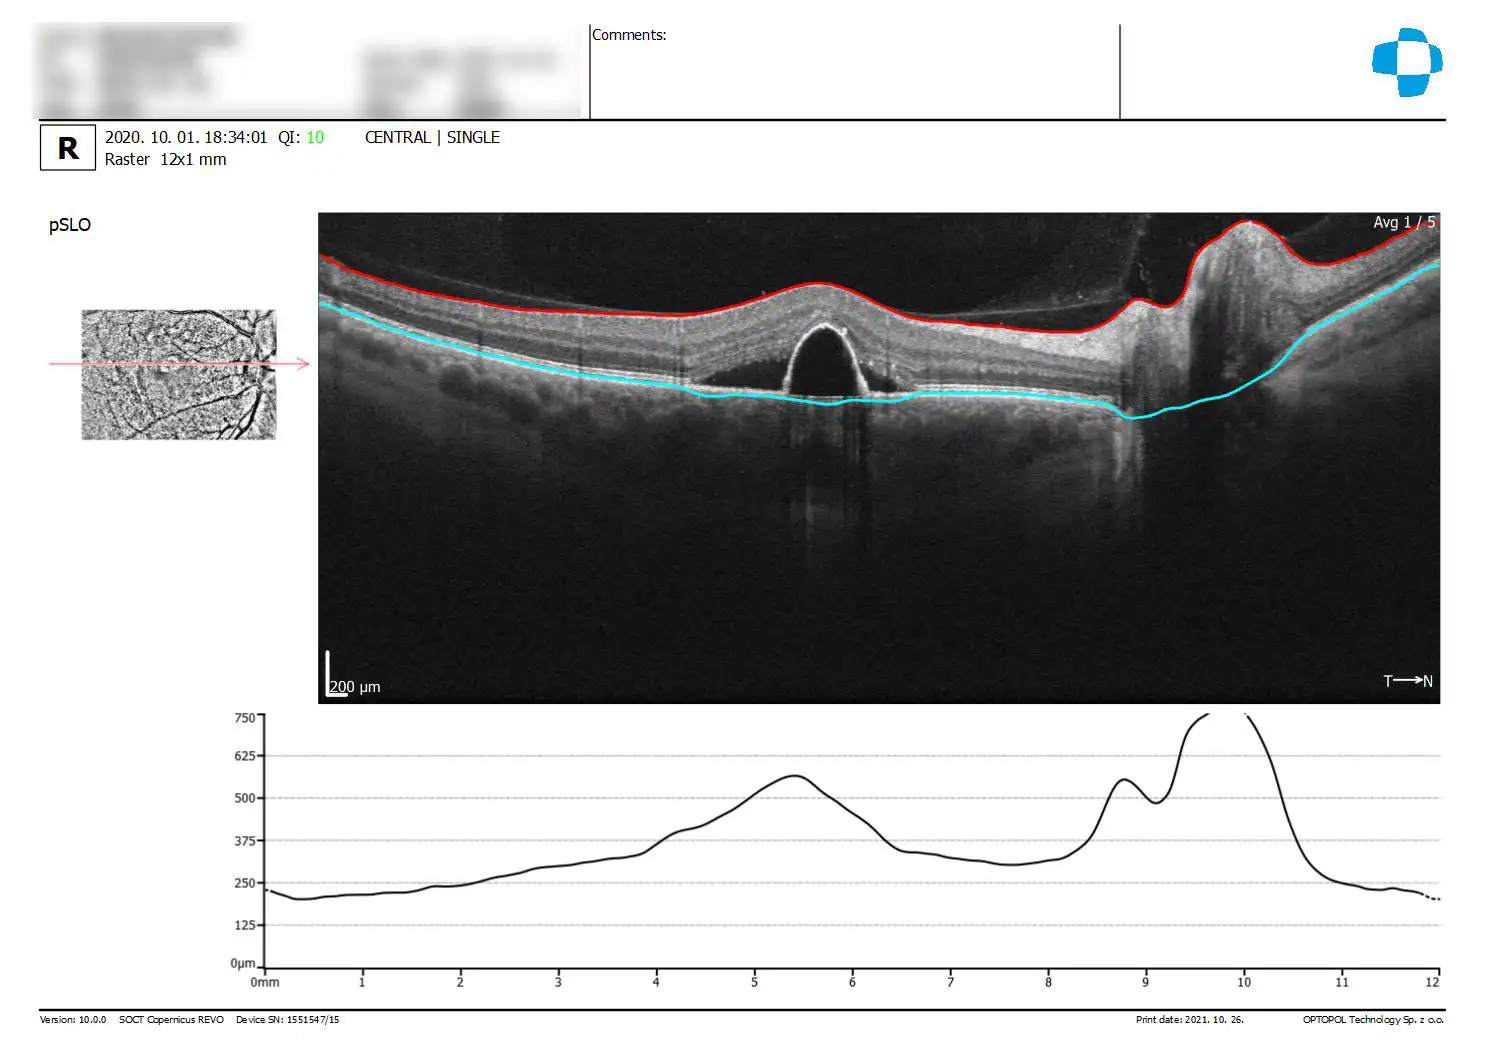

Mi az OCT vizsgálat?

Az OCT (optikai koherencia tomográfia) egy szemészeti vizsgálati módszer, amely lehetővé teszi a szem belsejének részletes, rétegenkénti vizsgálatát. Az OCT egy non-invazív, gyors és fájdalommentes vizsgálat, amelyet általában a szemész végez.